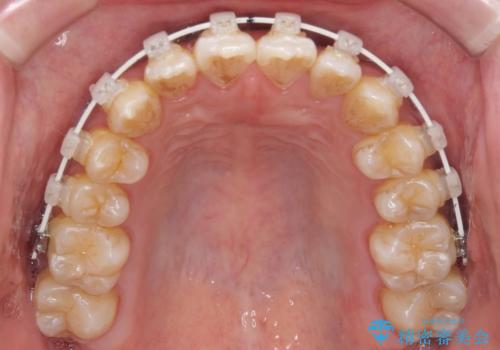

- 矯正装置

- 審美装置

- 治療期間

- 1年

矯正治療は上下全顎を行うことが大前提ですが、費用などの点から、今回は部分矯正を選択することとなりました。

患者様本人は咬みにくさを感じていないようですが、部分矯正は咬み合わせの改善が困難であることが多く、咬みにくさが残ることがあります。